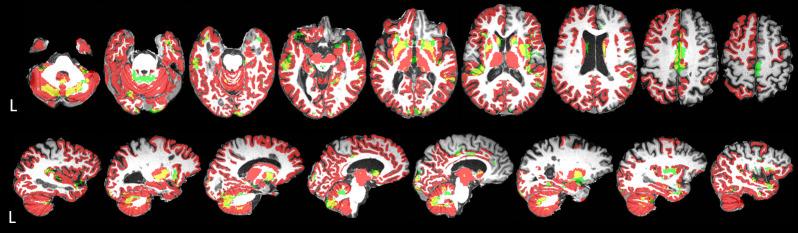

Recurrent neuroinflammation in relapsing-remitting MS (RRMS) is thought to lead to neurodegeneration, resulting in progressive disability. Repeated magnetic resonance imaging (MRI) of the brain provides non-invasive measures of atrophy over time, a key marker of neurodegeneration. This study investigates regional neurodegeneration of the brain in recently-diagnosed RRMS using volumetry and voxel-based morphometry (VBM). RRMS patients (N = 354) underwent 3T structural MRI <6 months after diagnosis and 1-year follow-up, as part of the Scottish multicentre 'FutureMS' study. MRI data were processed using FreeSurfer to derive volumetrics, and FSL for VBM (grey matter (GM) only), to establish regional patterns of change in GM and normal-appearing white matter (NAWM) over time throughout the brain. Volumetric analyses showed a decrease over time (q<0.05) in bilateral cortical GM and NAWM, cerebellar GM, brainstem, amygdala, basal ganglia, hippocampus, accumbens, thalamus and ventral diencephalon. Additionally, NAWM and GM volume decreased respectively in the following cortical regions, frontal: 14 out of 26 regions and 16/26; temporal: 18/18 and 15/18; parietal: 14/14 and 11/14; occipital: 7/8 and 8/8. Left GM and NAWM asymmetry was observed in the frontal lobe. GM VBM analysis showed three major clusters of decrease over time: 1) temporal and subcortical areas, 2) cerebellum, 3) anterior cingulum and supplementary motor cortex; and four smaller clusters within the occipital lobe. Widespread GM and NAWM atrophy was observed in this large recently-diagnosed RRMS cohort, particularly in the brainstem, cerebellar GM, and subcortical and occipital-temporal regions; indicative of neurodegeneration across tissue types, and in accord with limited previous studies in early disease. Volumetric and VBM results emphasise different features of longitudinal lobar and loco-regional change, however identify consistent atrophy patterns across individuals. Atrophy measures targeted to specific brain regions may provide improved markers of neurodegeneration, and potential future imaging stratifiers and endpoints for clinical decision making and therapeutic trials.

复发缓解型多发性硬化症(RRMS)中反复发生的神经炎症被认为会导致神经退行性变,从而导致进行性残疾。对大脑进行重复磁共振成像(MRI)可随时间提供萎缩的非侵入性测量,这是神经退行性变的关键标志物。本研究使用体素形态计量学(VBM)对近期诊断的 RRMS 患者的大脑进行区域性神经退行性变研究。RRMS 患者(N=354)在诊断后 6 个月内和 1 年随访期间接受了 3T 结构 MRI,这是苏格兰多中心“未来 MS”研究的一部分。MRI 数据使用 FreeSurfer 进行处理,以得出体积测量值,并使用 FSL 进行 VBM(仅灰质(GM)),以建立整个大脑 GM 和正常外观的白质(NAWM)随时间变化的区域性模式。体积分析显示,随着时间的推移(q<0.05),双侧皮质 GM 和 NAWM、小脑 GM、脑干、杏仁核、基底节、海马体、伏隔核、丘脑和腹侧间脑的体积减少。此外,分别在以下皮质区域中,NAWM 和 GM 体积减少:额叶:26 个区域中有 14 个和 16/26;颞叶:18/18 个和 15/18;顶叶:14/14 个和 11/14;枕叶:7/8 个和 8/8。左侧 GM 和 NAWM 不对称发生在额叶。GM VBM 分析显示,随时间减少的三个主要聚类:1)颞叶和皮质下区域,2)小脑,3)前扣带和辅助运动皮质;以及枕叶内的四个较小聚类。在这个大型最近诊断的 RRMS 队列中观察到广泛的 GM 和 NAWM 萎缩,特别是在脑干、小脑 GM 和皮质下及颞枕叶区域;表明各种组织类型的神经退行性变与早期疾病的有限先前研究一致。体积和 VBM 结果强调了纵向脑叶和局部区域变化的不同特征,但在个体之间识别出一致的萎缩模式。针对特定脑区的萎缩测量可能提供更好的神经退行性变标志物,并为临床决策和治疗试验提供潜在的未来成像分层和终点。